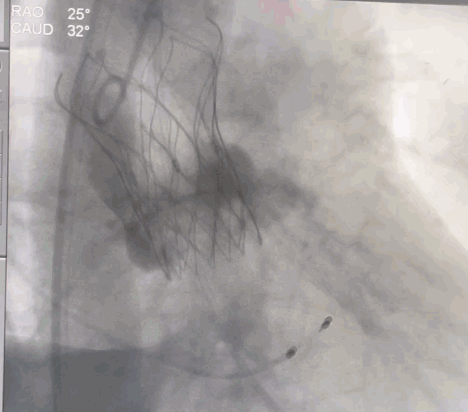

术中操作

经右侧颈动脉途径,直头导丝跨瓣成功后送入猪尾导管至左室,置入22F动脉鞘管。结合术前CT,装配好VitaFlow Liberty™27号瓣膜,在加硬导丝支撑下,送导管输送系统至主动脉根部并跨过主动脉瓣口,主动脉根部造影,确认瓣膜处于理想位置,在起搏下,经过慢释放、快释放及终释放,完成瓣膜释放过程。术后病人生命体征平稳,跨瓣压差明显改善,无瓣周漏。

瓣膜定位

瓣膜释放中